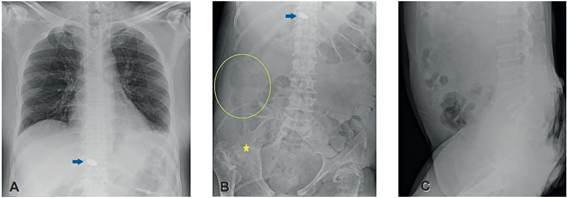

Recibimos un paciente de 54 años, con antecedente de lesión medular hace más de 20 años por herida por proyectil de arma de fuego y colecistectomía por laparotomía hacía cuatro meses, remitido de otra institución para manejo de ulcera sacra. Al examen físico se palpaba masa renitente en flanco derecho. La radiografía de abdomen informó “una burbuja gaseosa en el flanco y fosa ilíaca derecha, sugestiva de neumoperitoneo” (Figura 1), por lo que se solicitó una tomografía computarizada de abdomen (Figura 2), donde describían una colección multiloculada localizada en la gotera parietocólica derecha con extensión perihepática, en la fosa ilíaca derecha y la pared abdominal, de 20 x 8 x 6 cm con volumen calculado de 500 ml; extenso proceso inflamatorio que compromete los tejidos blandos de la región sacra, perineal y el ano, y en la unión posterior de la articulación sacroilíaca derecha, defecto en la continuidad de los tejidos blandos, la cual probablemente estaba comunicada con la colección en la gotera parietocólica ipsilateral.

Figura 1. Serie de abdomen donde mencionan que existe una burbuja gaseosa en el flanco y fosa ilíaca derecha, sugestiva de neumoperitoneo (circulo verde). Además, hay destrucción y resorción de la cabeza femoral derecha (junto a la estrella amarilla), asociado con luxación coxofemoral, y alteración en la esfericidad de la cabeza femoral izquierda, la cual presenta osificaciones heterotópicas en el espacio articular coxofemoral. Diástasis de la sínfisis púbica en aproximadamente 5 cm. Proyectil de arma de fuego localizado en el margen posterior del cuerpo vertebral T12 (flecha azul).